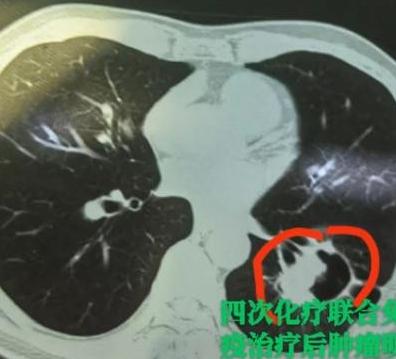

查出局部晚期肺癌,一开始被告知已经没法手术了……谁能想到,几个月之后复查,肺上的肿瘤竟然几乎消失了!从“不能手术”到“肿瘤明显缩小、成功手术”,他们到底经历了什么? 最近我做了4台肺癌手术,其中有3台都是经过“新辅助治疗”之后,才争取到手术机会的。 这几位患者中,有2位是先做了“新辅助免疫+化疗”,1位是做了“新辅助靶向治疗”。 很多朋友可能听说过靶向治疗——先做基因检测,如果有突变,配上合适的靶向药,吃下去效果往往很明显。但如果没有相应突变,可能就要考虑“免疫治疗+化疗”这个组合拳。 免疫治疗现在技术已经比较成熟,其实就像我们平常打点滴一样,输的是一种抗体(PD-1 或 PDL-1抑制剂)。 它的作用,简单说就是:帮我们的免疫系统“认出”癌细胞——因为癌细胞会伪装自己,躲避免疫系统的攻击,而免疫药物可以撕掉这层伪装,让免疫细胞重新识别并消灭肿瘤。 这3位患者在经过药物治疗后,虽然肿瘤明显缩小了,但由于淋巴结之前有粘连、局部有疤痕,手术其实仍然非常难做。 好在最后都顺利切掉了病灶。更令人欣慰的是,病理结果回来显示:切下来的组织里已经找不到活的肿瘤细胞了。 这也给很多晚期肺癌患者带来了新希望,即使一开始不能手术,通过有效的药物治疗,也有机会达到手术条件,甚至实现临床治愈。[玫瑰][谢谢]